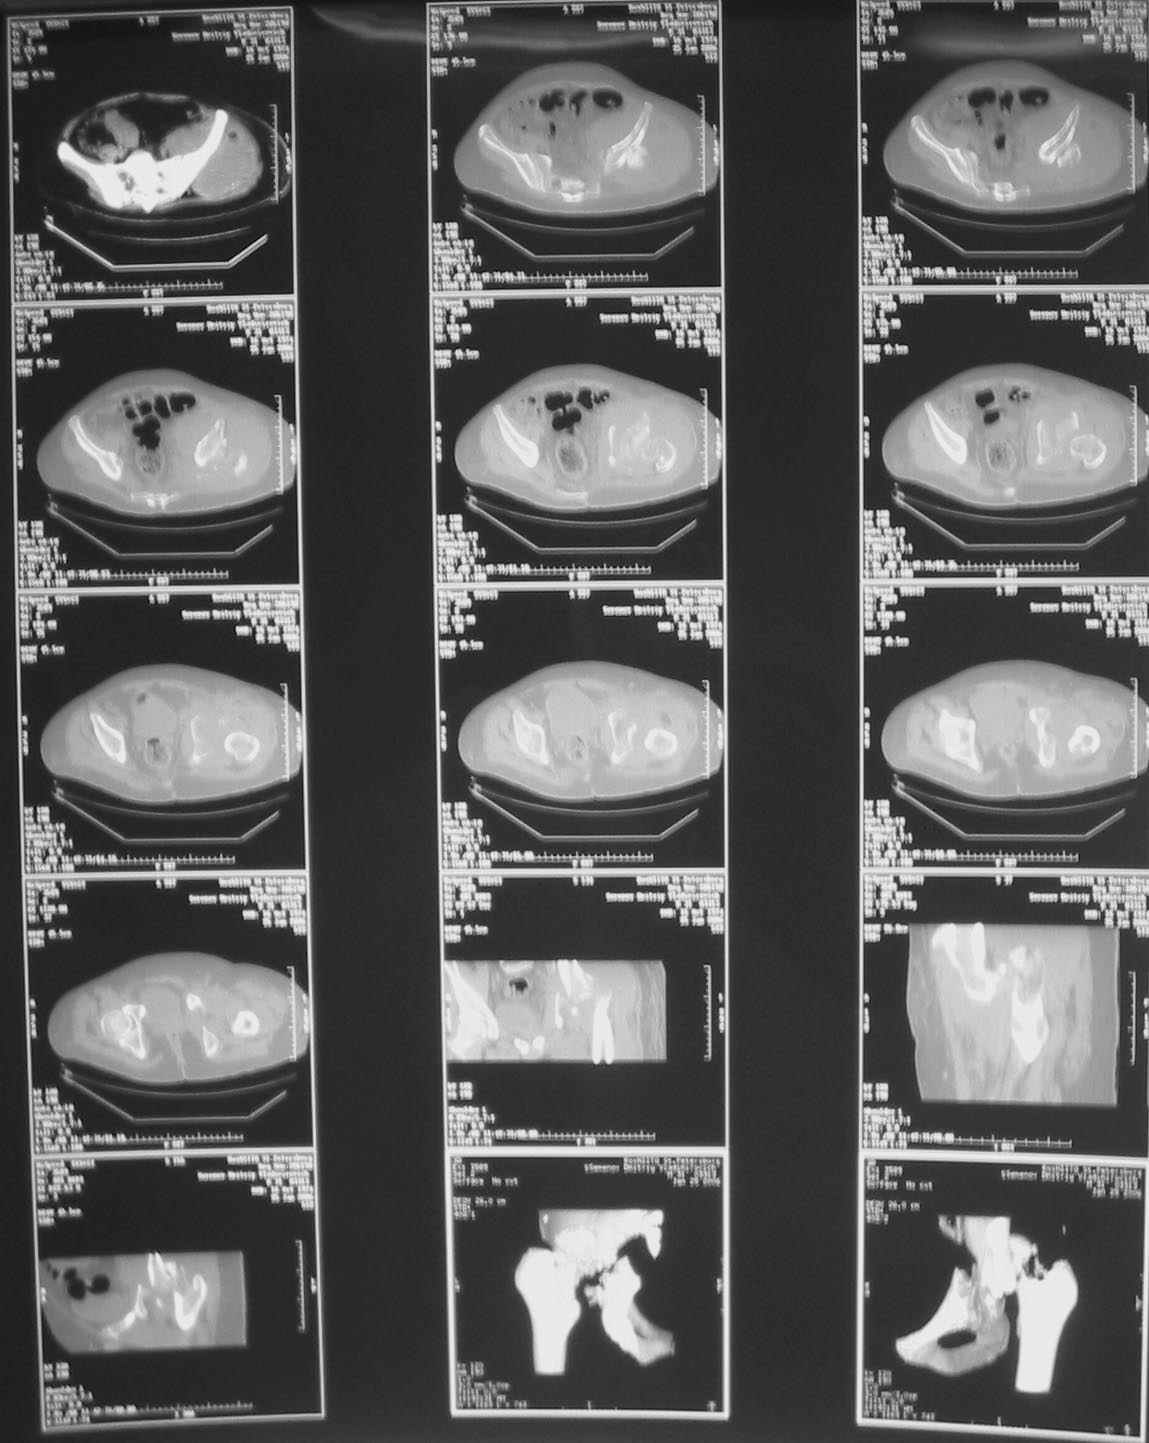

Таз+шейка

Дорогие коллеги, Поступил пациент, 5 месяцев, как сломался.

Поступил для эндопротезирования, но наши корифеи засомневались, не собрать ли сначала таз. Есть ли смысл собирать аппаратом закрыто?